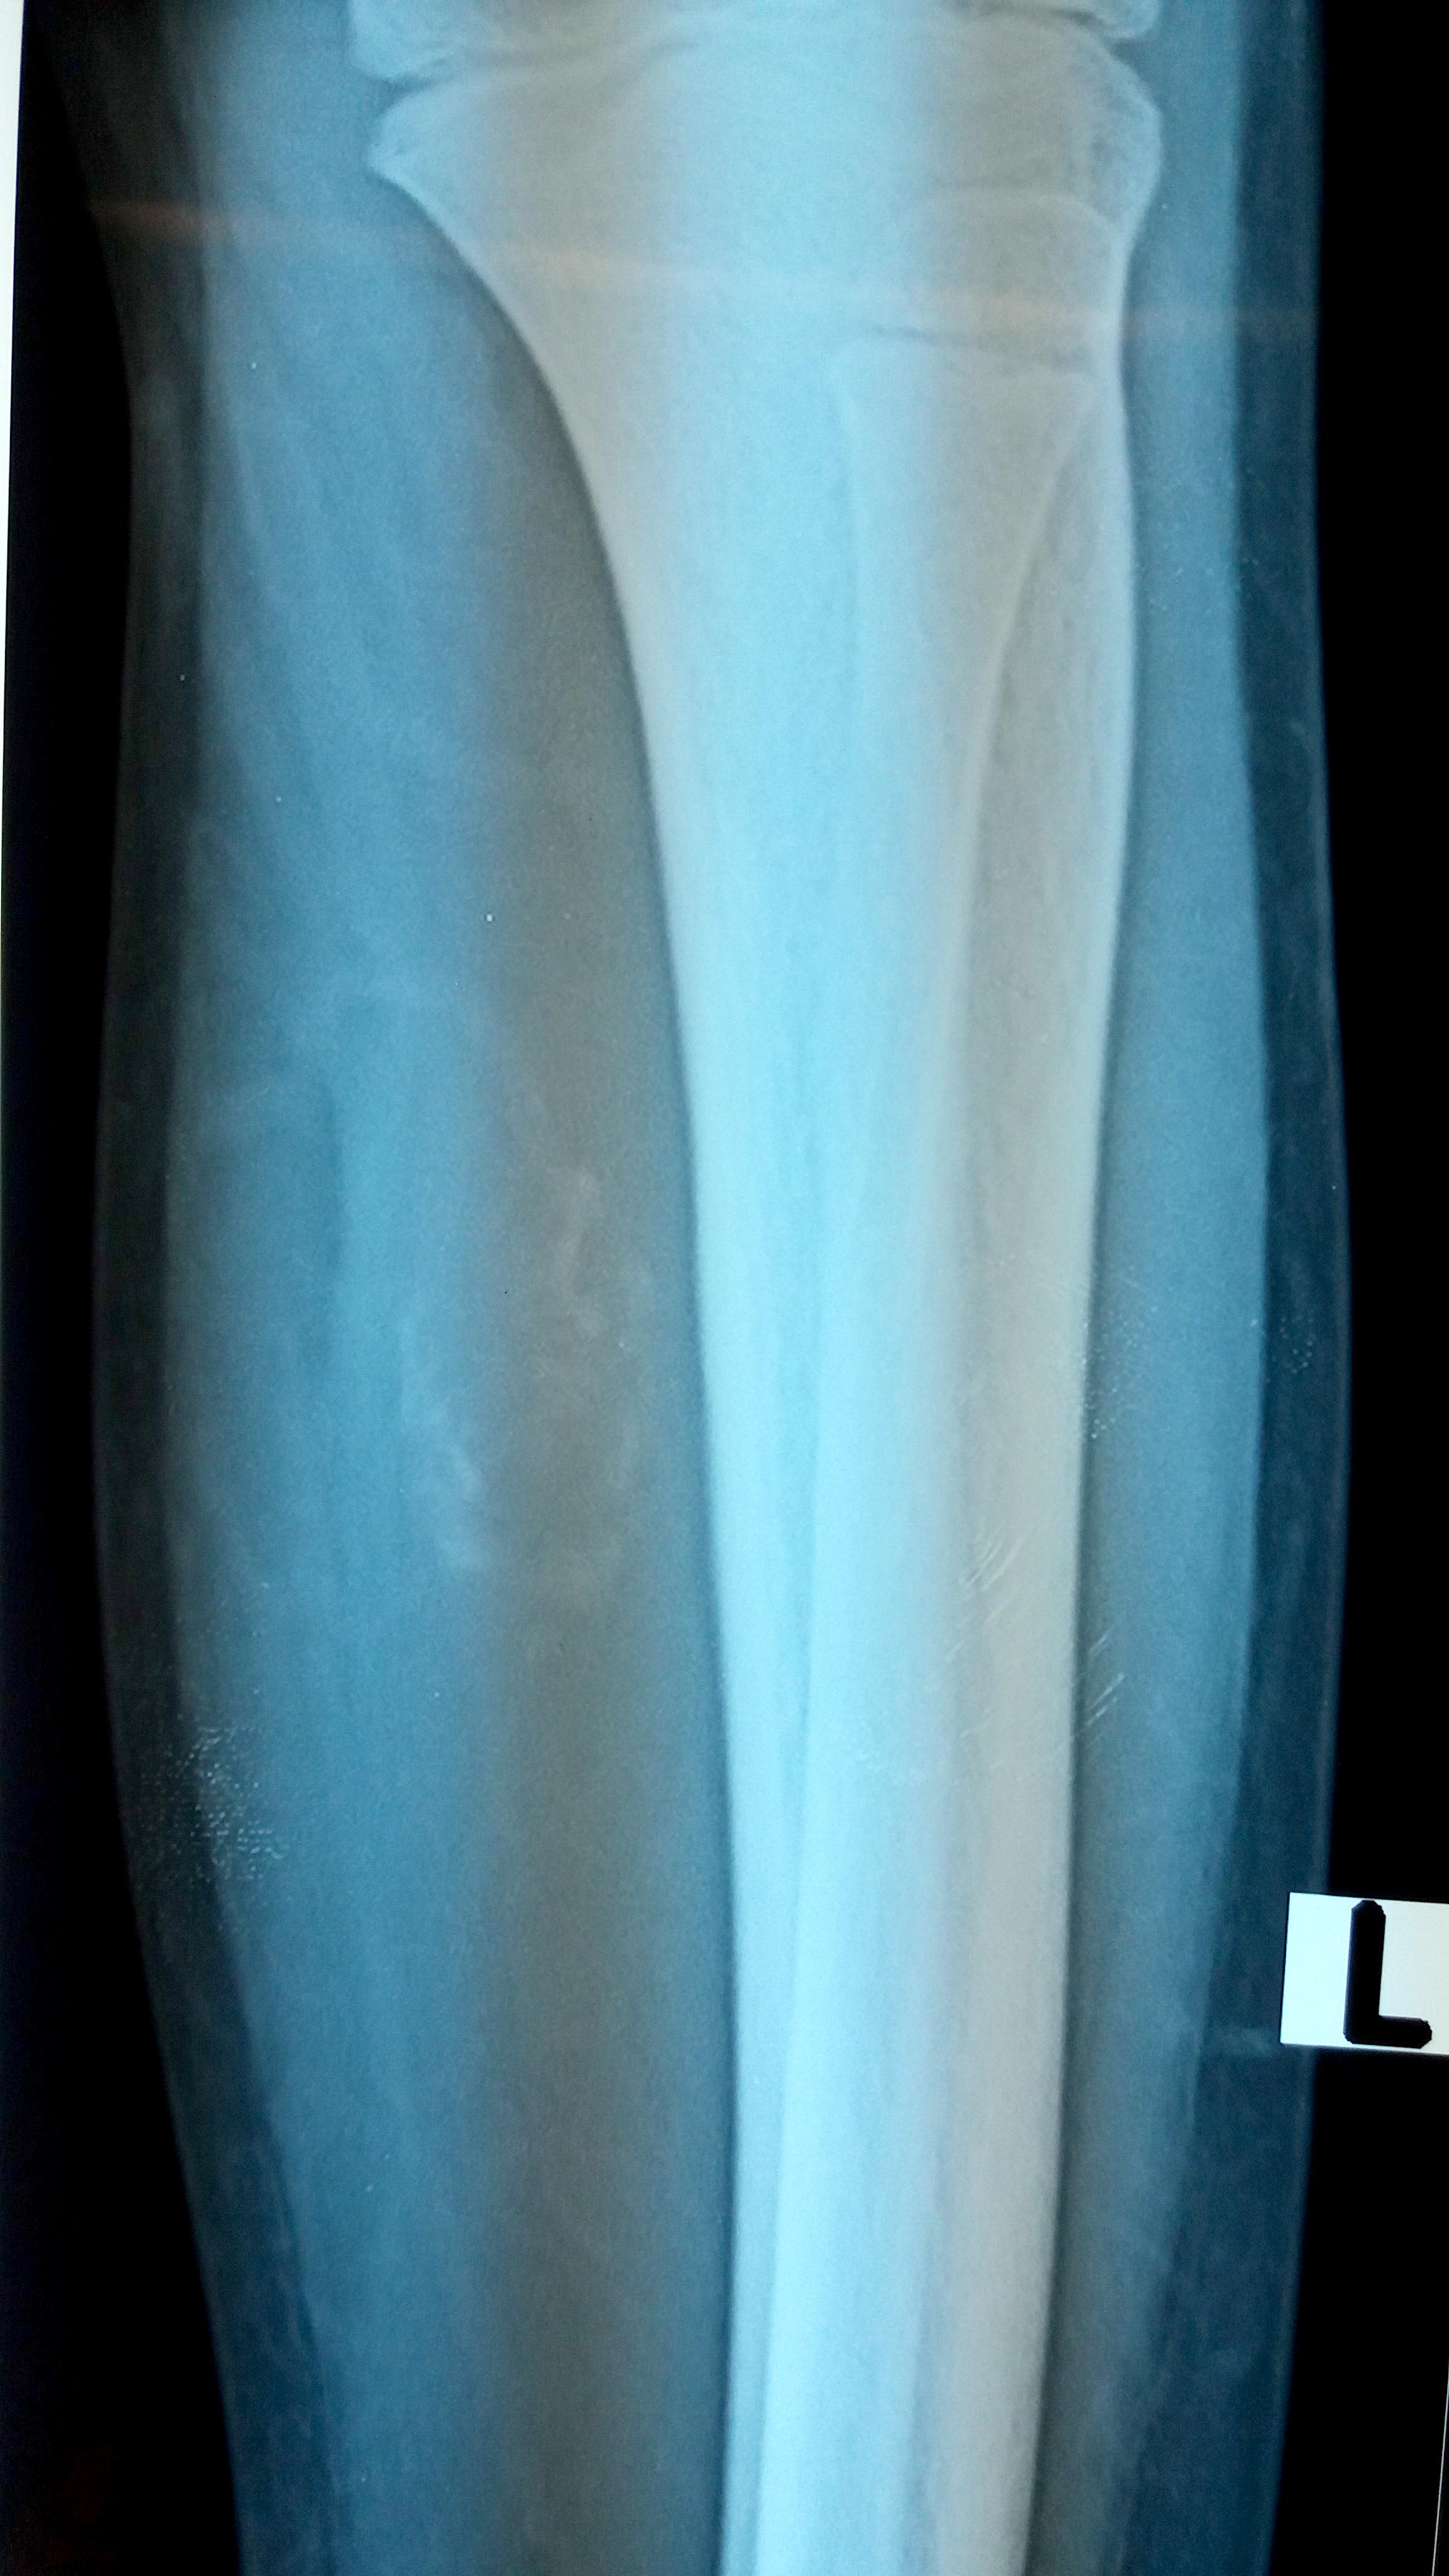

Radiology description

- Early stage:

- Xray: normal to faint calcification (flocculent radiopacities: dotted veil pattern)

- CT scan: soft tissue edema

- MRI: isodense on T1 and hyperintense on T2

- Intermediate stage:

- Xray: peripheral calcified rim with central lucency

- CT scan: peripheral mineralization with central low attenuation (calcification proceeds from periphery to center)

- MRI: isodense / hypodense to adjacent skeletal muscle on all images

- Mature, late stage:

- Xray: diffuse soft tissue calcification

- CT scan: diffuse ossification pattern (even in late lesions, the central core may remain uncalcified)

- MRI: well defined soft tissue mass and isodense to fat on all images

- References: Curr Sports Med Rep 2018;17:290, J Clin Orthop Trauma 2021;17:123

Radiology images